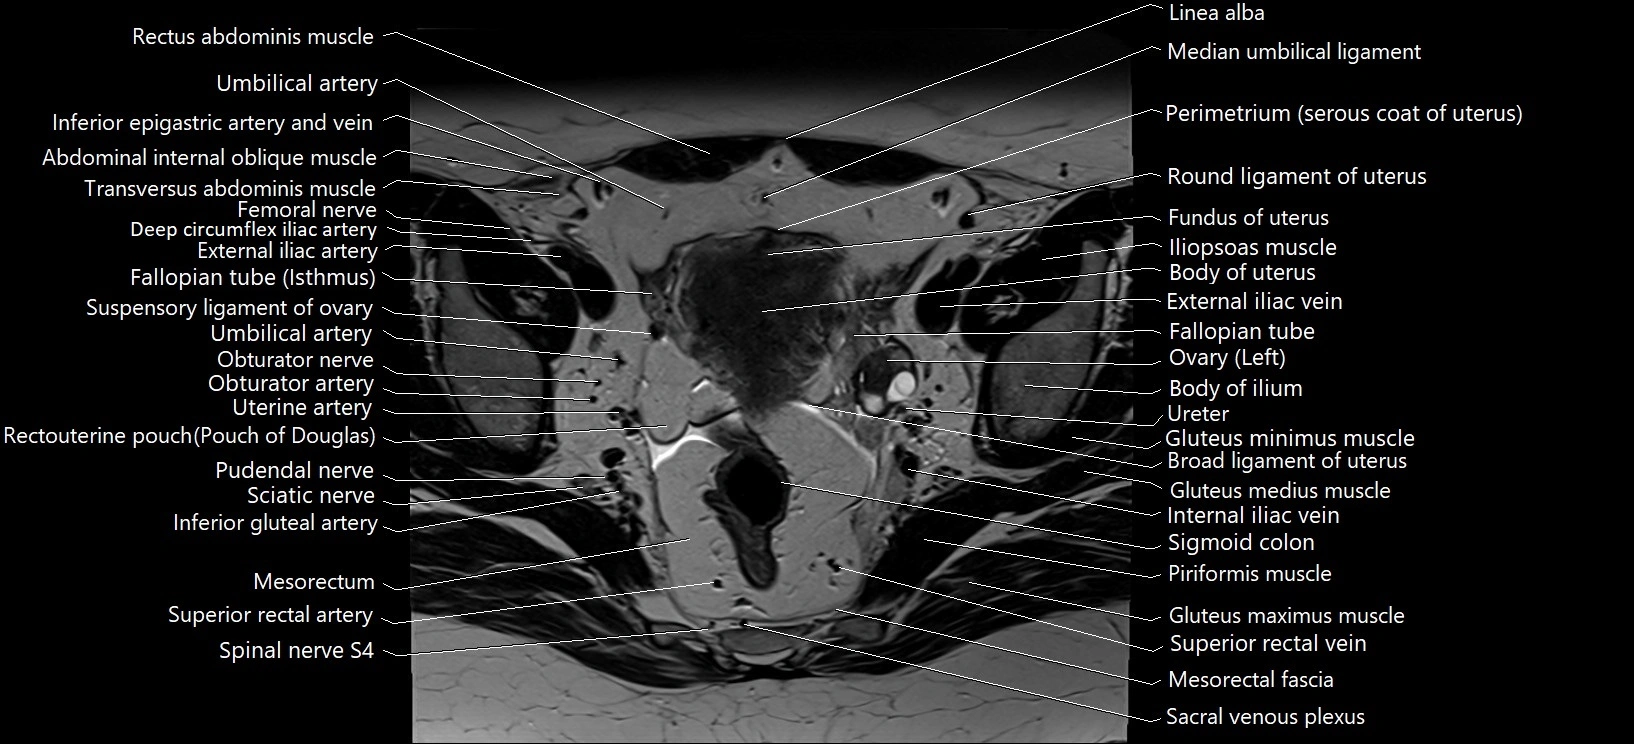

- Body of ilium

- Body of ischium

- Broad ligament of uterus

- External iliac artery

- External iliac vein

- Fallopian tube

- Fundus of uterus

- Gluteus medius muscle

- Gluteus medius tendon

- Gluteus minimus muscle

- Iliopsoas muscle

- Internal iliac vein

- Median umbilical ligament

- Mesorectal fascia

- Mesorectum

- Obturator nerve

- Obturator artery

- Perimetrium of uterus

- Piriformis muscle

- Pudendal nerve

- Rectouterine pouch (pouch of Douglas)

- Round ligament of uterus

- Sciatic nerve

- Sigmoid colon

- Superior rectal artery

- Superior rectal vein

- Suspensory ligament of ovary

- Umbilical artery

- Uterine artery